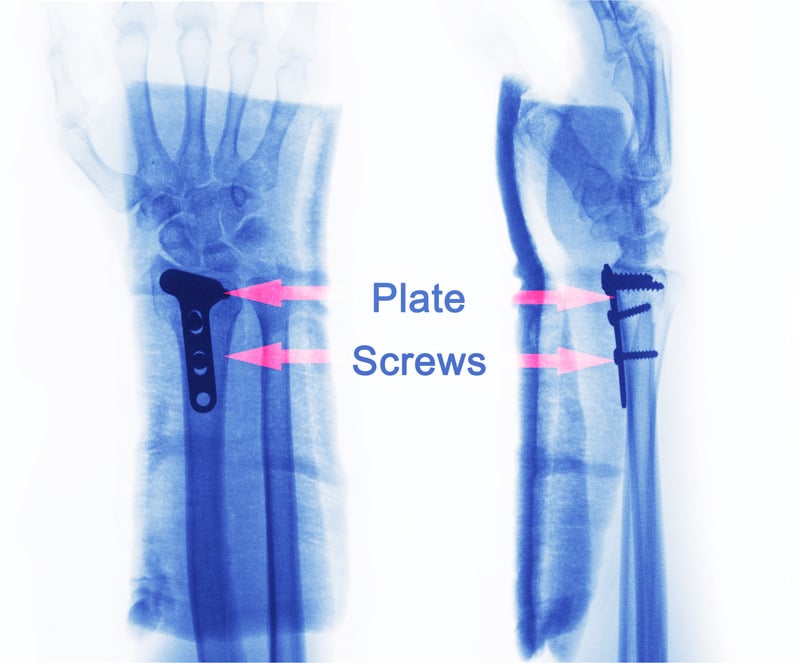

• Εσωτερική Σταθεροποίηση (Οστεοσύνθεση): Αυτή η μέθοδος περιλαμβάνει την τοποθέτηση μεταλλικών πλακών, βιδών ή ράβδων για να

σταθεροποιηθεί το κάταγμα εσωτερικά. Η ακριβής ευθυγράμμιση των οστών επιτρέπει την ταχύτερη και πιο σταθερή επούλωση.